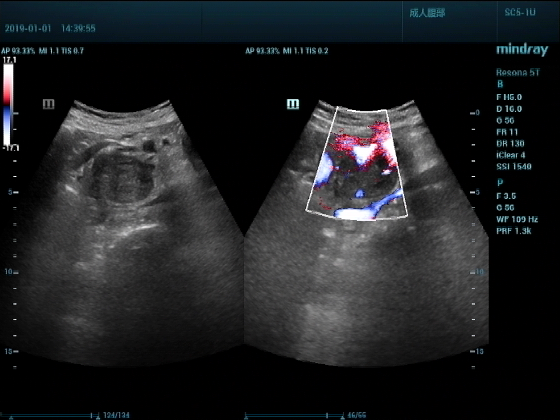

超声入门贴959--胰头癌并胰管扩张

男,88岁,腹部隐疼2个月加重3天来诊